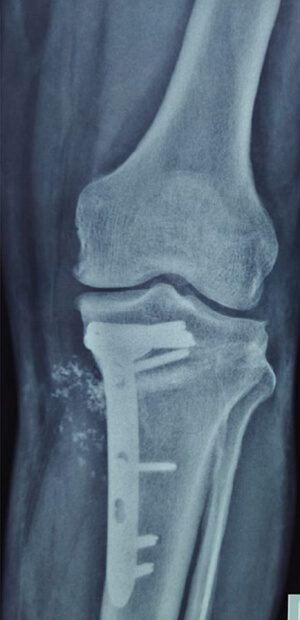

DEFORMITY CORRECTION

TRAUMA